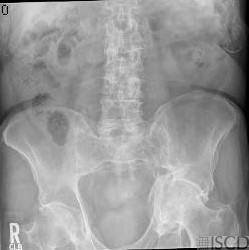

The accompanying radiograph shows the left acetabula protrusio.

This is a patient with acetabular protrusion. The right hip would need to be used for the DXA scan. Protrusio acetabuli can be primary and is often associated with osteoarthritis. It may also be familial. Secondary causes include Paget’s disease, psoriatic arthropathy, rheumatoid arthritis, ankylosing spondylitis, osteomalacia and rickets, osteogenesis imperfecta, Marfan syndrome, trauma, and hemophilia.